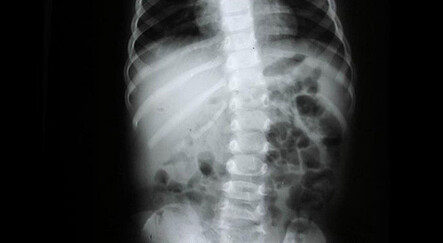

Hastalığın erken belirtilerinden biri olabilen kas seğirmelerinin bir iç kas grubunda gerçekleşmesi halinde çıplak gözle fark edilemediğini göz önüne alan bilim insanları, kas seğirmelerini gözlemleyebilmek için geleneksel ultrason cihazlarını kullandı.

100 ALS hastası ve 100 sağlıklı bireydeki 15 kas grubunun hareketlerini gözlemleyen ekip sırt, kol ve baldır kasları dahil 8 kas grubunda anormal seğirme yaşayan deneklerin yüzde 95,6'sının ALS belirtileri gösterdiğini saptadı.